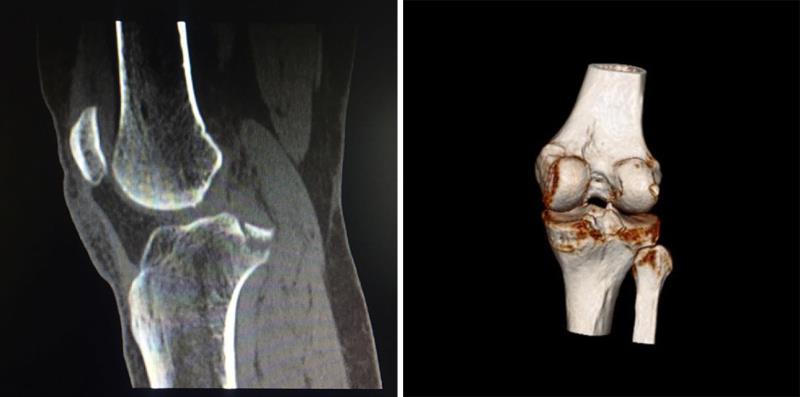

术后3月复查X线片提示骨折达到骨愈合

术后,患者右膝关节伸直位固定1个月后,在支具保护下逐渐负重行走,术后8周便去除支具完全负重行走。术后3个月复查,右膝关节X线片检查提示右膝后交叉韧带止点撕脱骨折达到骨愈合,右膝关节功能各项指标接近术前,大限度的恢复了患者右膝关节功能。经过8个月的随访,患者及其家属对手术效果非常满意,取得了良好的临床效果。